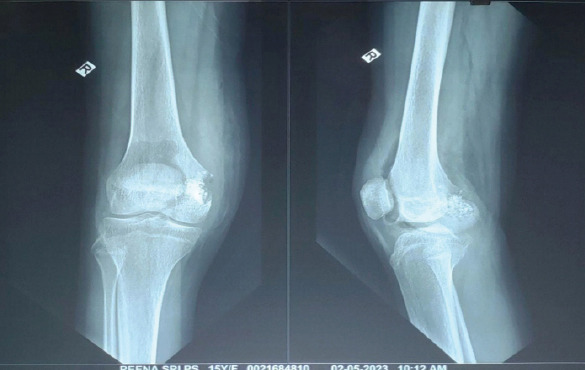

Case report: A 15-year-old female presented with progressive right knee pain of 6 months' duration, worsened by weight-bearing and minimally relieved by analgesics. Clinical examination revealed tenderness and immobile swelling in the region of the medial femoral condyle. Imaging showed characteristic "chicken-wire" calcification, and computed tomography-guided biopsy confirmed chondroblastoma. The patient underwent extended curettage, iliac crest bone grafting, and the use of synthetic bone substitutes. Post-operative rehabilitation showed a good recovery in range of motion and limb function, with no recurrence at follow-up.